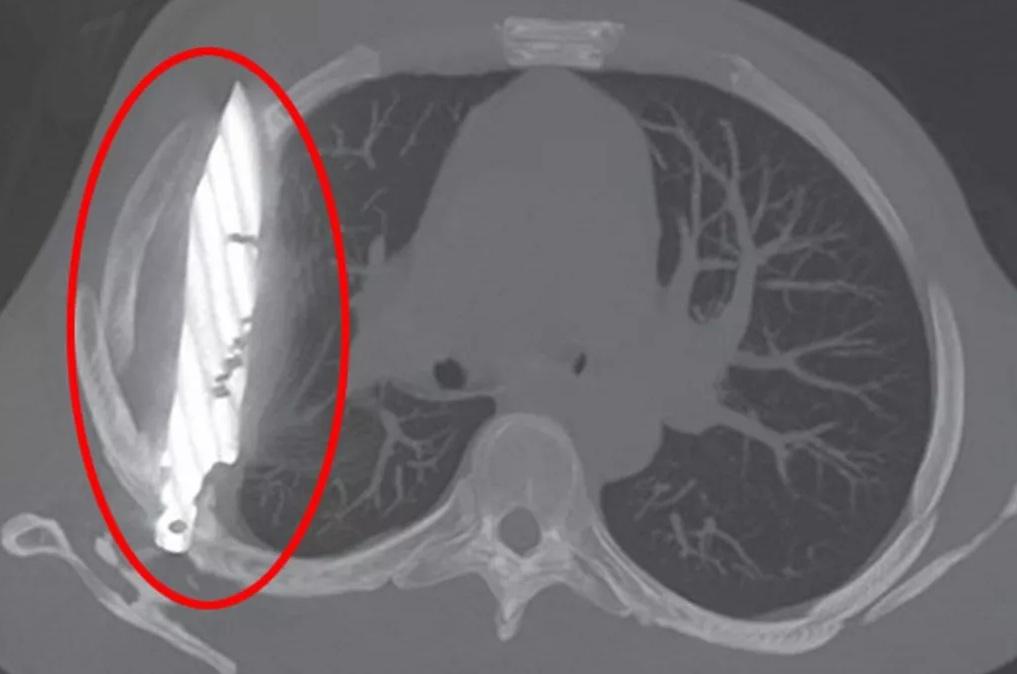

胸部X光影像可見,有一把刀插在男病人胸腔內。(互聯網)

胸部X光檢查結果顯示,有一把刀插在病人胸腔內。從X光影像可見,這把刀從右肩胛骨插入,奇蹟地避開重要器官。